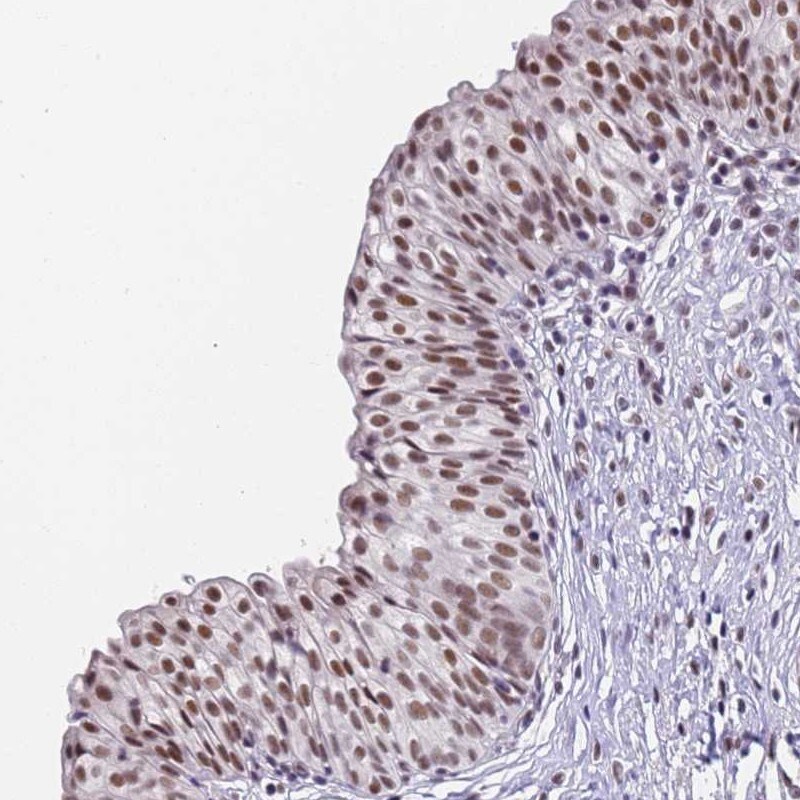

Supportive validation

- Submitted by

- Invitrogen Antibodies (provider)

- Main image

- Experimental details

- Immunohistochemical analysis of FNBP4 in human urinary bladder using FNBP4 Polyclonal Antibody (Product # PA5-59035) shows moderate nuclear positivity in urothelial cells.